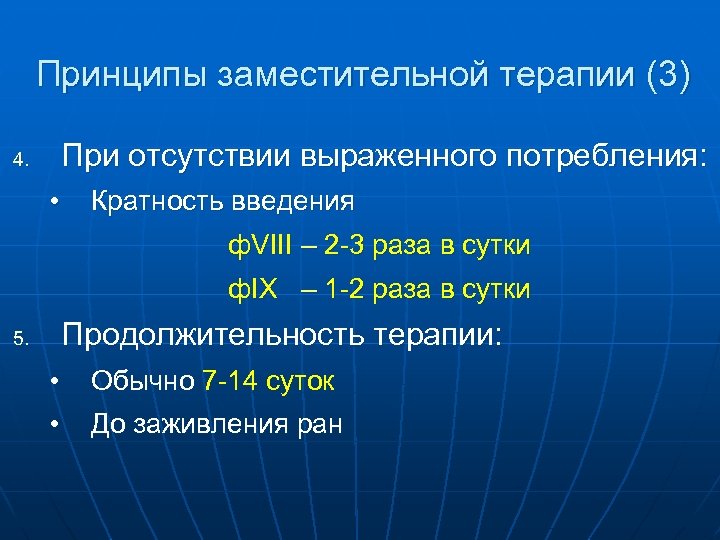

Принципы заместительной терапии (3) При отсутствии выраженного потребления: 4. • Кратность введения ф. VIII – 2 -3 раза в сутки ф. IX – 1 -2 раза в сутки Продолжительность терапии: 5. • • Обычно 7 -14 суток До заживления ран